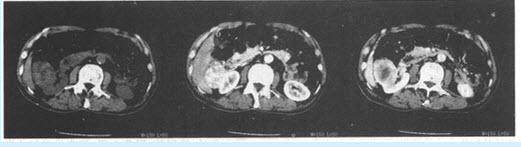

女,35岁,下腹部不适,CT扫描子宫增大呈分叶状,CT扫描如图所示,首先应该考虑的是()

A:子宫肌瘤

B:子宫内膜癌

C:葡萄胎

D:妊娠

E:子宫肌腺瘤